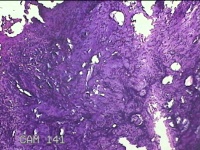

肛周脓壁组织

性别

男

年龄

46岁

临床诊断

1.肛周脓肿 2.混合痔 3.肛裂

一般病史

肛周疼痛2天。

标本名称

大体所见

灰白暗红色不规则碎组织2.2x0.3x0.2cm一块,表面糜烂,位面灰白暗红色,质软。

像良性病变,所提供图片不具有诊断价值。